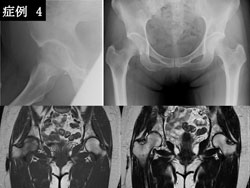

症例4 : 58 歳、女性。誘因なく右股部痛が出 現。単純X 線にて右大腿骨頭の輪郭不明瞭な骨萎縮像を認めました。MRI にてT2 強調像で 低信号は認めず一過性大腿骨頭萎縮症の診断を 得ました。保存的治療にて治癒しました。